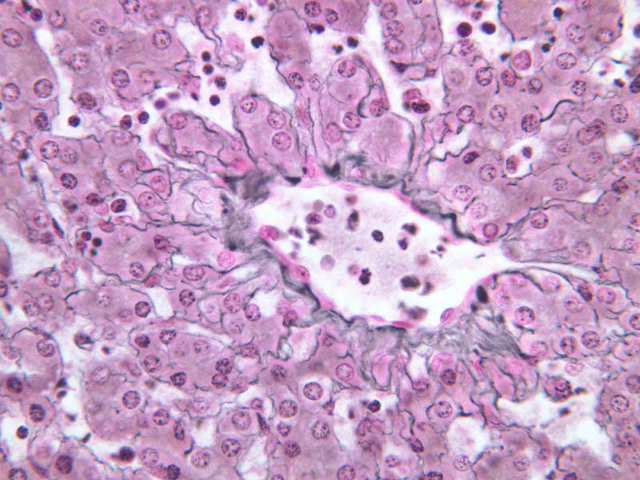

Although H & E staining permits ready identification of the islets of Langerhans, it does not permit differentiation of the various cell types that comprise the islets (B-36, H&E [10x, 20x, 40x-labeled]). There are no slides in the class collection that permit identification of all of the cell types of the endocrine pancreas. However, the sections on slides B-37 and B-40 permit specific identification of two cell types. Slide B-37 has been stained by the aldehyde fuchsin technique, which lends a magenta coloration to the granules of the insulin-producing B-cells. All other cells in the islets stain a dirty orange color (B-37 [10x, 20x, 40x] [10x, 20x, 40x]). Most of these orange-colored cells are the glucagon-secreting A-cells; however, you should bear in mind that somatostatin-secreting D-cells, as well as APUD cells that secrete pancreatic polypeptide are also scattered about the islet. The section on slide B-40 has been prepared by a silver impregnation method that renders some of the APUD cells in the islets (which appear as “clear cells” in ordinary preparations) dark brown or black (B-40 [10x, 20x, 40x]).

The specimen on slide B-39 was prepared by perfusing India ink into the blood stream of an animal. Examine this specimen with an eye to understanding how the capillary beds of the exocrine and endocrine portions of the pancreas differ (B-39, Ink/H&E [10x, 20x-labeled] [10x] [10x, 20x]).